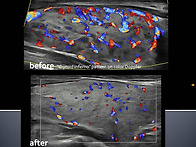

| 유방, 갑상선 초음파 스캔 및 병리과정.. | sonoedu | 280 | 26.02.07 |